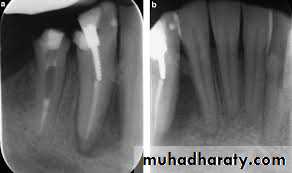

PERSISTENT/SECONDARY ENDODONTIC INFECTIONS

persistent intraradicular infections are caused by microorganisms that resisted intracanal antimicrobial procedures and survived in the treated canal.Involved microorganisms are remnants of a primary or secondary infection. The latter, in turn, is caused by microorganisms

that at some time entered the root canal system secondary to clinical intervention .The moment can be during treatment,

between appointments, or even after root canal filling. In any circumstance, if penetrating microorganisms manage to adapt

themselves to the new environment, surviving and flourishing, a secondary infection is established. Species involved can be

oral microorganisms or not, depending on the source of secondary infection

Bacteria at the Root Obturation Stage

Bacteria persisting in the root canal after chemomechanical procedures or intracanal medication will not always maintainan infectious process. This statement is supported by evidence that some apical periodontitis lesions healed even after bacteria were isolated from the canal at the obturation stage. There are some possible explanations :

♦ Residual bacteria may die after obturation because of toxic effects of the filling material or sealer, access denied to

nutrients, or disruption of bacterial ecology.

♦ Residual bacteria may be present in quantities and virulence subcritical to sustaining periradicular inflammation.

♦ Residual bacteria remain in locations where access to periradicular tissues is denied